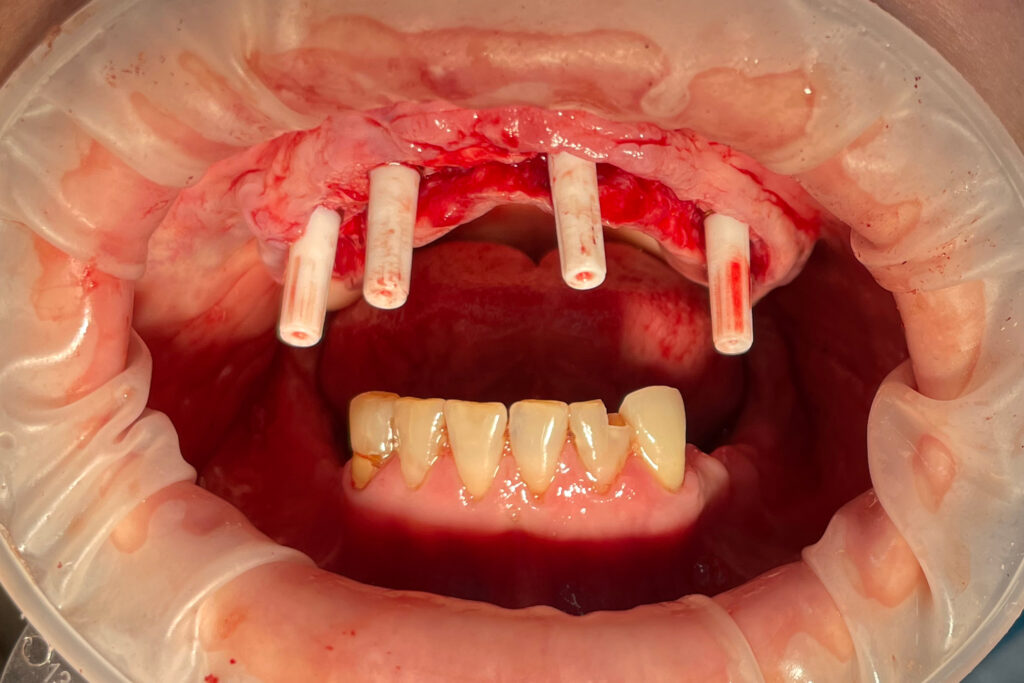

Процесс работы

Что было сделано:

После проведенной консультации было принято решение о проведении комплексной имплантации по системе All-on-6.

После установки 6ти имплантантов Megagen AnyRidge были сняты оттиски для изготовления металлоакрилового протеза.

Процесс имплантации

Это фото может содержать тяжелый для восприятия контент